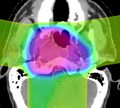

Dose volume histogram in Slicer